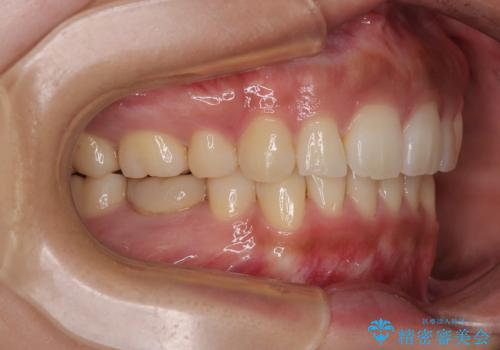

口元の突出感が改善されてことで、下唇に引っかかっていた上顎前歯も気にならなくなりました。